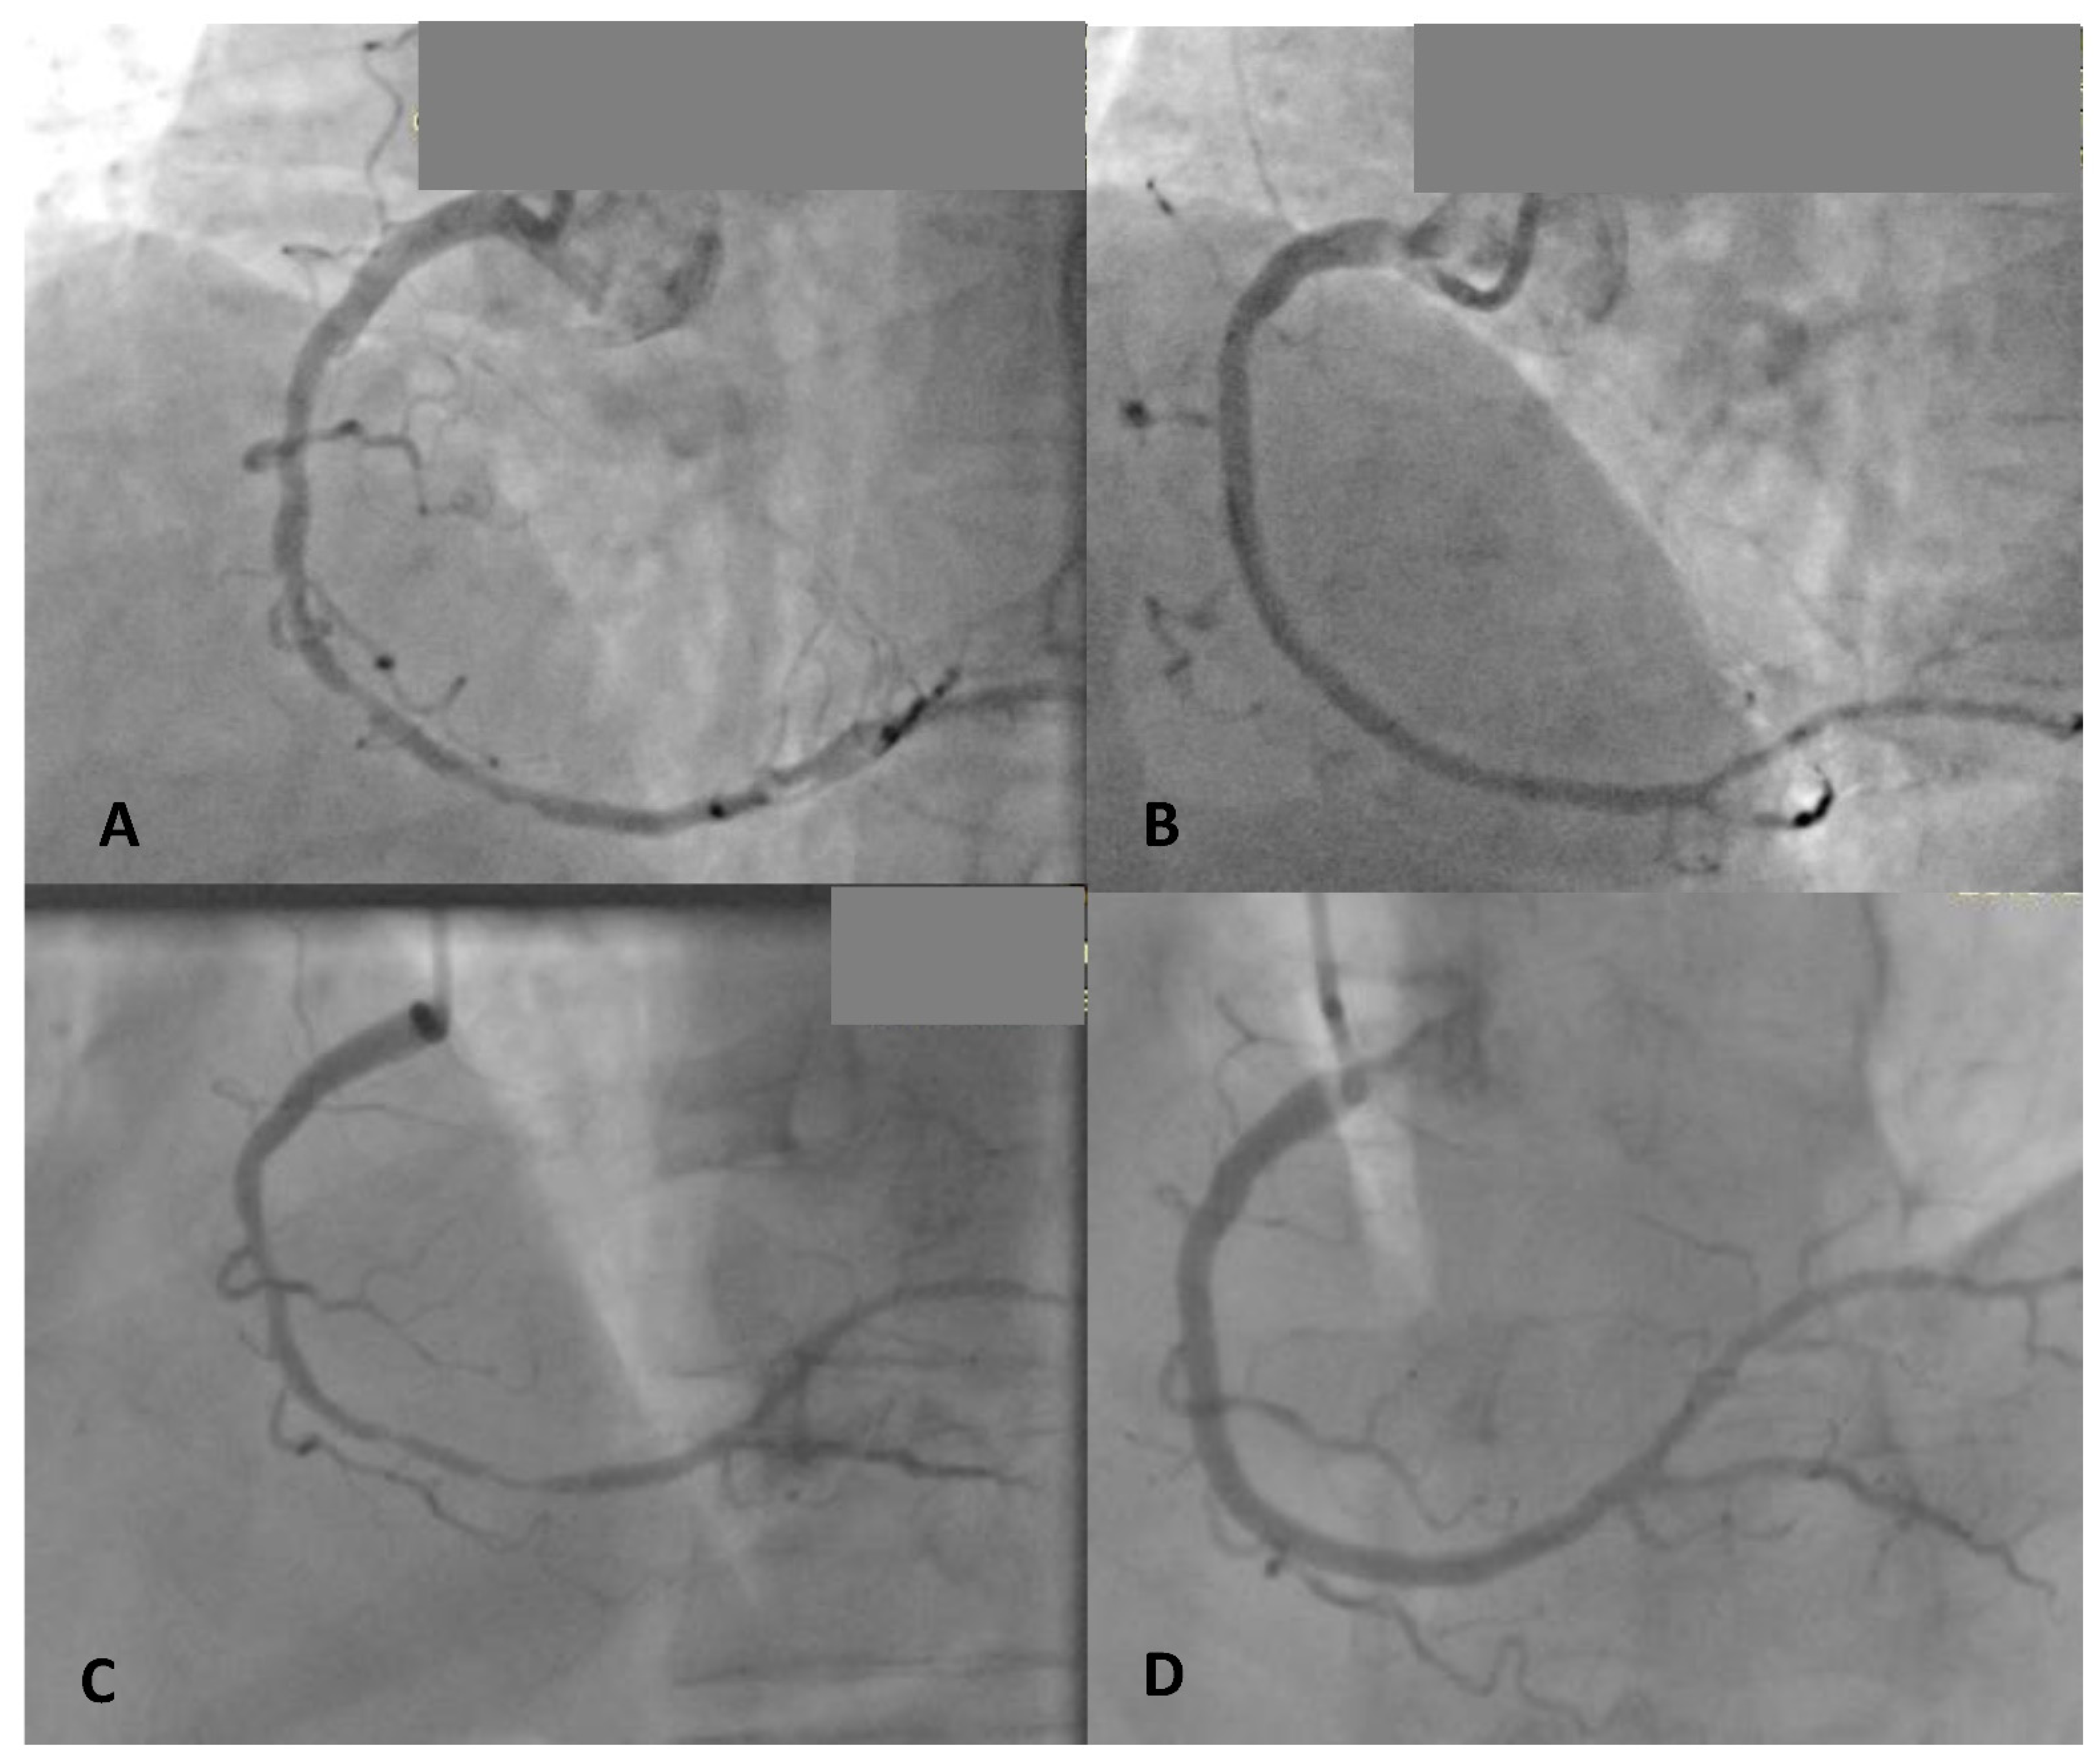

Figure 2.

Coronary angiography before and after implantation of 2 Magmaris BVS in the right coronary artery (A—diffuse and long stenosis in mid RCA, B—after two 3.0 × 25 mm Magmaris implantations) and 6 months later (C—diffuse in-scaffold restenosis) with diffuse in-scaffold restenosis treated successfully with 2 DES (D).